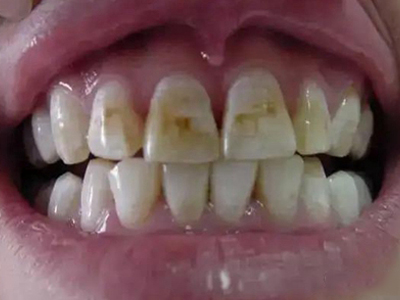

酸蚀症牙齿有大量黄斑及白斑图

患酸蚀症时,牙齿表面可出现大量黄斑及白斑,交错分布,形状不规则,境界不清楚,牙面还有少量竖行裂纹,是牙骨质受破坏的表现,需积极防控致病因素。